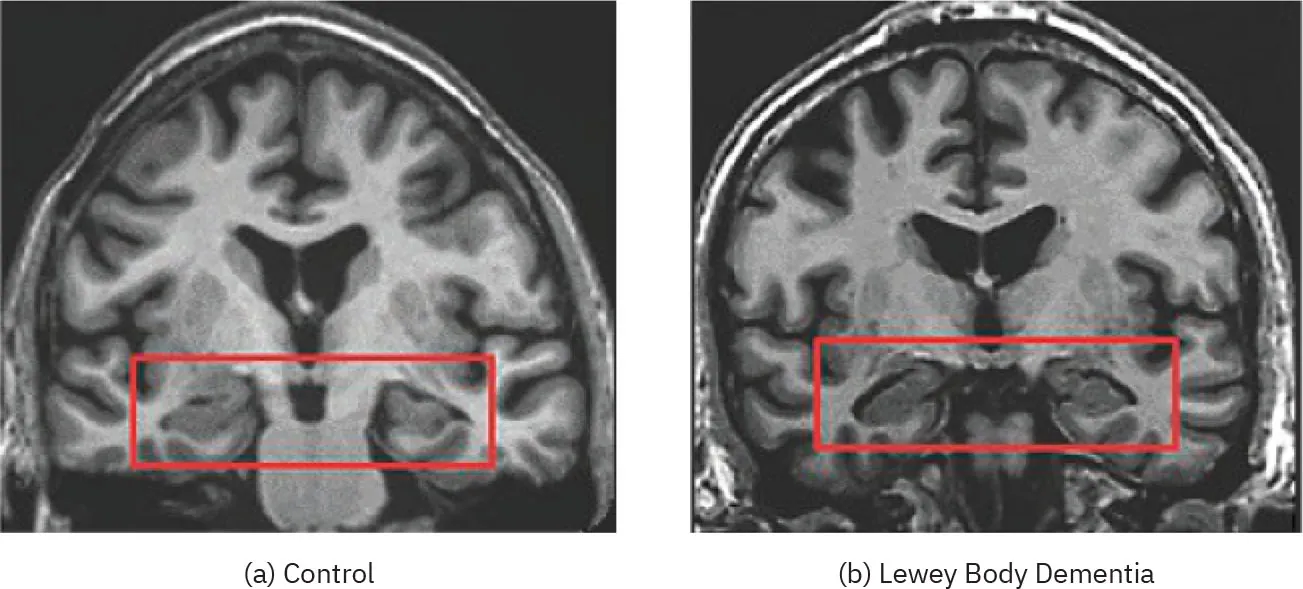

Lewy body dementia is the third most common type of dementia. It’s caused by deposits of a specific protein found in the cortex of the brain (Figure 15.19). These protein deposits, called Lewy bodies, have been linked to loss of the neurons responsible for producing neurochemicals, such as acetylcholine (which plays a role in attention, learning, and memory) and dopamine (related to experiencing pleasure, motivation, sleep, and cognition). The most common symptoms of Lewy body dementia are visual hallucinations, difficulty paying attention, and difficulty with thinking and judgment. These tend to change drastically over short periods of time, going from nearly nonexistent to severe and back again without any apparent reason. Other symptoms are related to motor skills and include stiffness, slow movement, and shaking (Orad & Shiner, 2022).

(a) An image shows a healthy brain with areas of tissue and a box outlining the hippocampus. (b) An image shows a brain with Lewy body dementia, where the hippocampus is smaller than the first image.

Figure 15.19 (a) This image shows a healthy brain with the hippocampus outlined in red. (b) In this image of a brain afflicted with Lewy body dementia, notice that the hippocampus (inside the red box) is smaller, indicating that brain tissue has died. (credit a and b: modification of work “MRI Alzheimer Disease and Dementia with Lewy Bodies” by McKeith IG, Boeve BF, Dickson DW, et al./Wikimedia Commons, CC BY 4.0)

Lewy body dementia is difficult to predict because its cause is unclear. Though the risk increases with age, research has not identified any behavioral or lifestyle risk factors. The condition is progressive and fatal, with no effective treatment or cure.

More recent research using magnetic resonance imaging has supported this earlier work, indicating that people eventually diagnosed with Alzheimer’s disease show more loss of neurons in the temporal lobe than in other regions of the brain. Other types of dementia are characterized by other patterns of neuron loss; for example, Lewy body dementia appears to disproportionately affect the parietal lobe (Orad & Shiner, 2022).